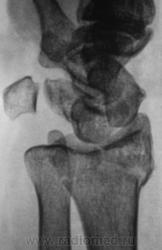

Травма.   Пациент направлен на рентгенографию лучезапястного сустава.